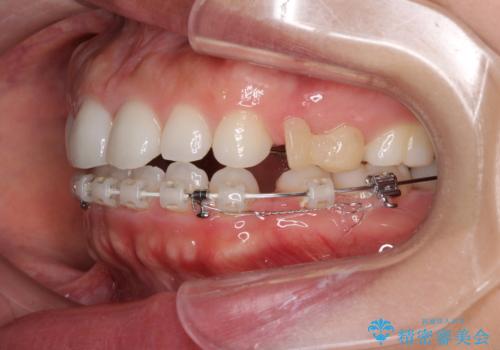

- 矯正装置

- ハーフリンガル

表側のワイヤー矯正に比べると治療期間は長く、費用も高額となりますが、どうしても目立たせたくないという方にはお勧めの抜歯矯正です。